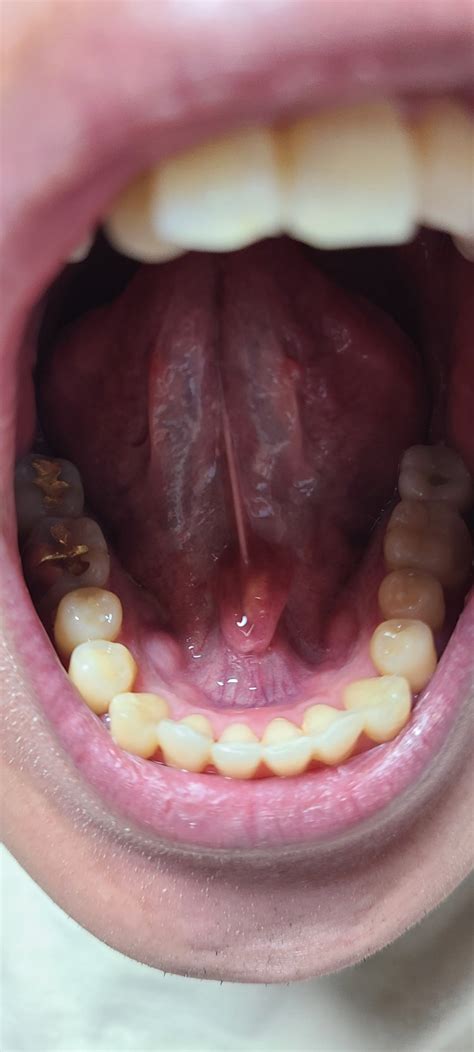

혀아래 침샘? 줄? 통증

한국어로 "혀밑 침샘? 줄? 통증"이라고 설명하시는 증상은 턱밑샘이나 설하선, 심지어 타액관이나 기타 구강 조직의 문제와 관련이 있는 것 같습니다.

1. 악하선 문제 악하선은 턱뼈 아래에 위치하며 악하관을 통해 타액을 방출합니다. 이 샘의 자극성 염증이나 감염은 혀 아래 부위에 통증 부종과 압통을 유발할 수 있습니다.

2. 설하선 문제 설하선은 입 바닥 아래에 위치하며 타액도 생성합니다. 이 샘의 자극성 염증이나 감염은 위에서 설명한 것과 유사한 증상을 유발할 수 있습니다.

3. 타액관 문제 턱밑샘에서 입으로 타액을 운반하는 턱밑관 또는 와튼관이 막히거나 염증이 생겨 해당 부위에 통증이 붓고 압통이 발생할 수 있습니다.

4. 구강 조직 문제 입의 혀저 또는 설소대와 같은 다른 구강 조직도 유사한 증상을 유발할 수 있습니다.

문제를 더 잘 진단하고 치료하려면 치과의사와 상담하는 것이 도움이 될 것입니다. 또는 이비인후과 전문의에게 철저한 검사와 평가를 받으세요.